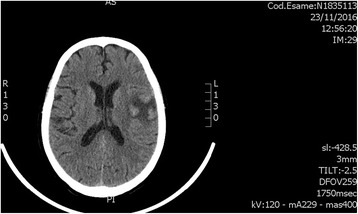

Serial brain CT scans performed in the following days showed ischemic hypodensity involving the left Sylvian fissure (Fig. 1).

Fig. 1.

Ischemic hypodensity involving the left Sylvian fissure on brain computed tomography